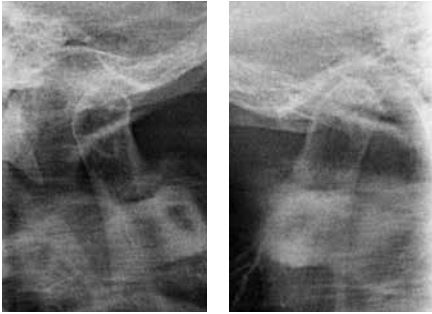

Đánh giá vị trí hàm dưới bằng X-quang khớp thái dương hàm (TMJ) hoặc CBCT

Để đánh giá vị trí của lồi cầu trong hố khớp thái dương hàm, độ ổn định của vị trí hàm dưới cũng như phát hiện các vùng thấu quang gợi ý tình trạng viêm, sự dẹt của lồi cầu hoặc hình thành gai xương (osteophyte) thì chụp X-quang khớp thái dương hàm hoặc CT chùm tia hình nón là những phương tiện hữu ích.

Dựa trên kết quả của lần thăm khám ban đầu này, chúng ta có thể dự đoán liệu có thể đạt được hiệu quả hít dính tốt ở hàm dưới hay không, hoặc liệu có cần thiết kế một loại hàm giả điều trị đặc biệt hay không.